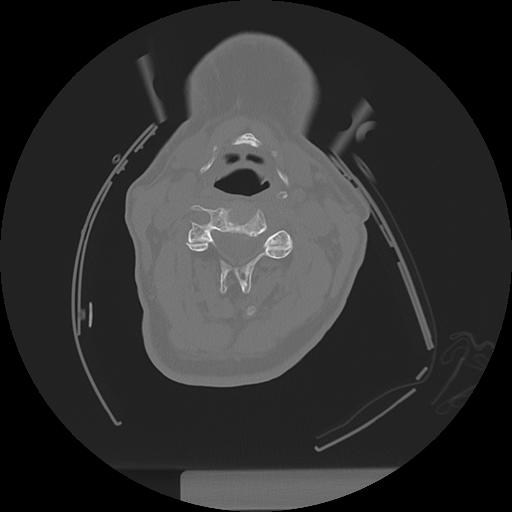

11 HUESO,,Axial,2.0,HUESO,,